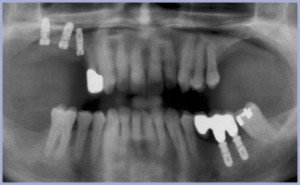

A metà 2003 giunge alla nostra osservazione paziente maschio di anni 54 portatore di parodontite settorialmente grave e complicata da lesioni infraossee circumferenziali purulente a carico di alcuni elementi dentari (15, 16, 35, 36, 47): questi appaiono senza possibilità di recupero, come evidenziabile da indagine radiologica iniziale (fig. 1), e vengono sottoposti ad estrazione.

La ortopantomografia iniziale mostra altresì una grave perdita ossea verticale a carico delle selle edentule superiori sia nella componente crestale, sia nella componente sinusale.

- Fig. 1 – Opt iniziale